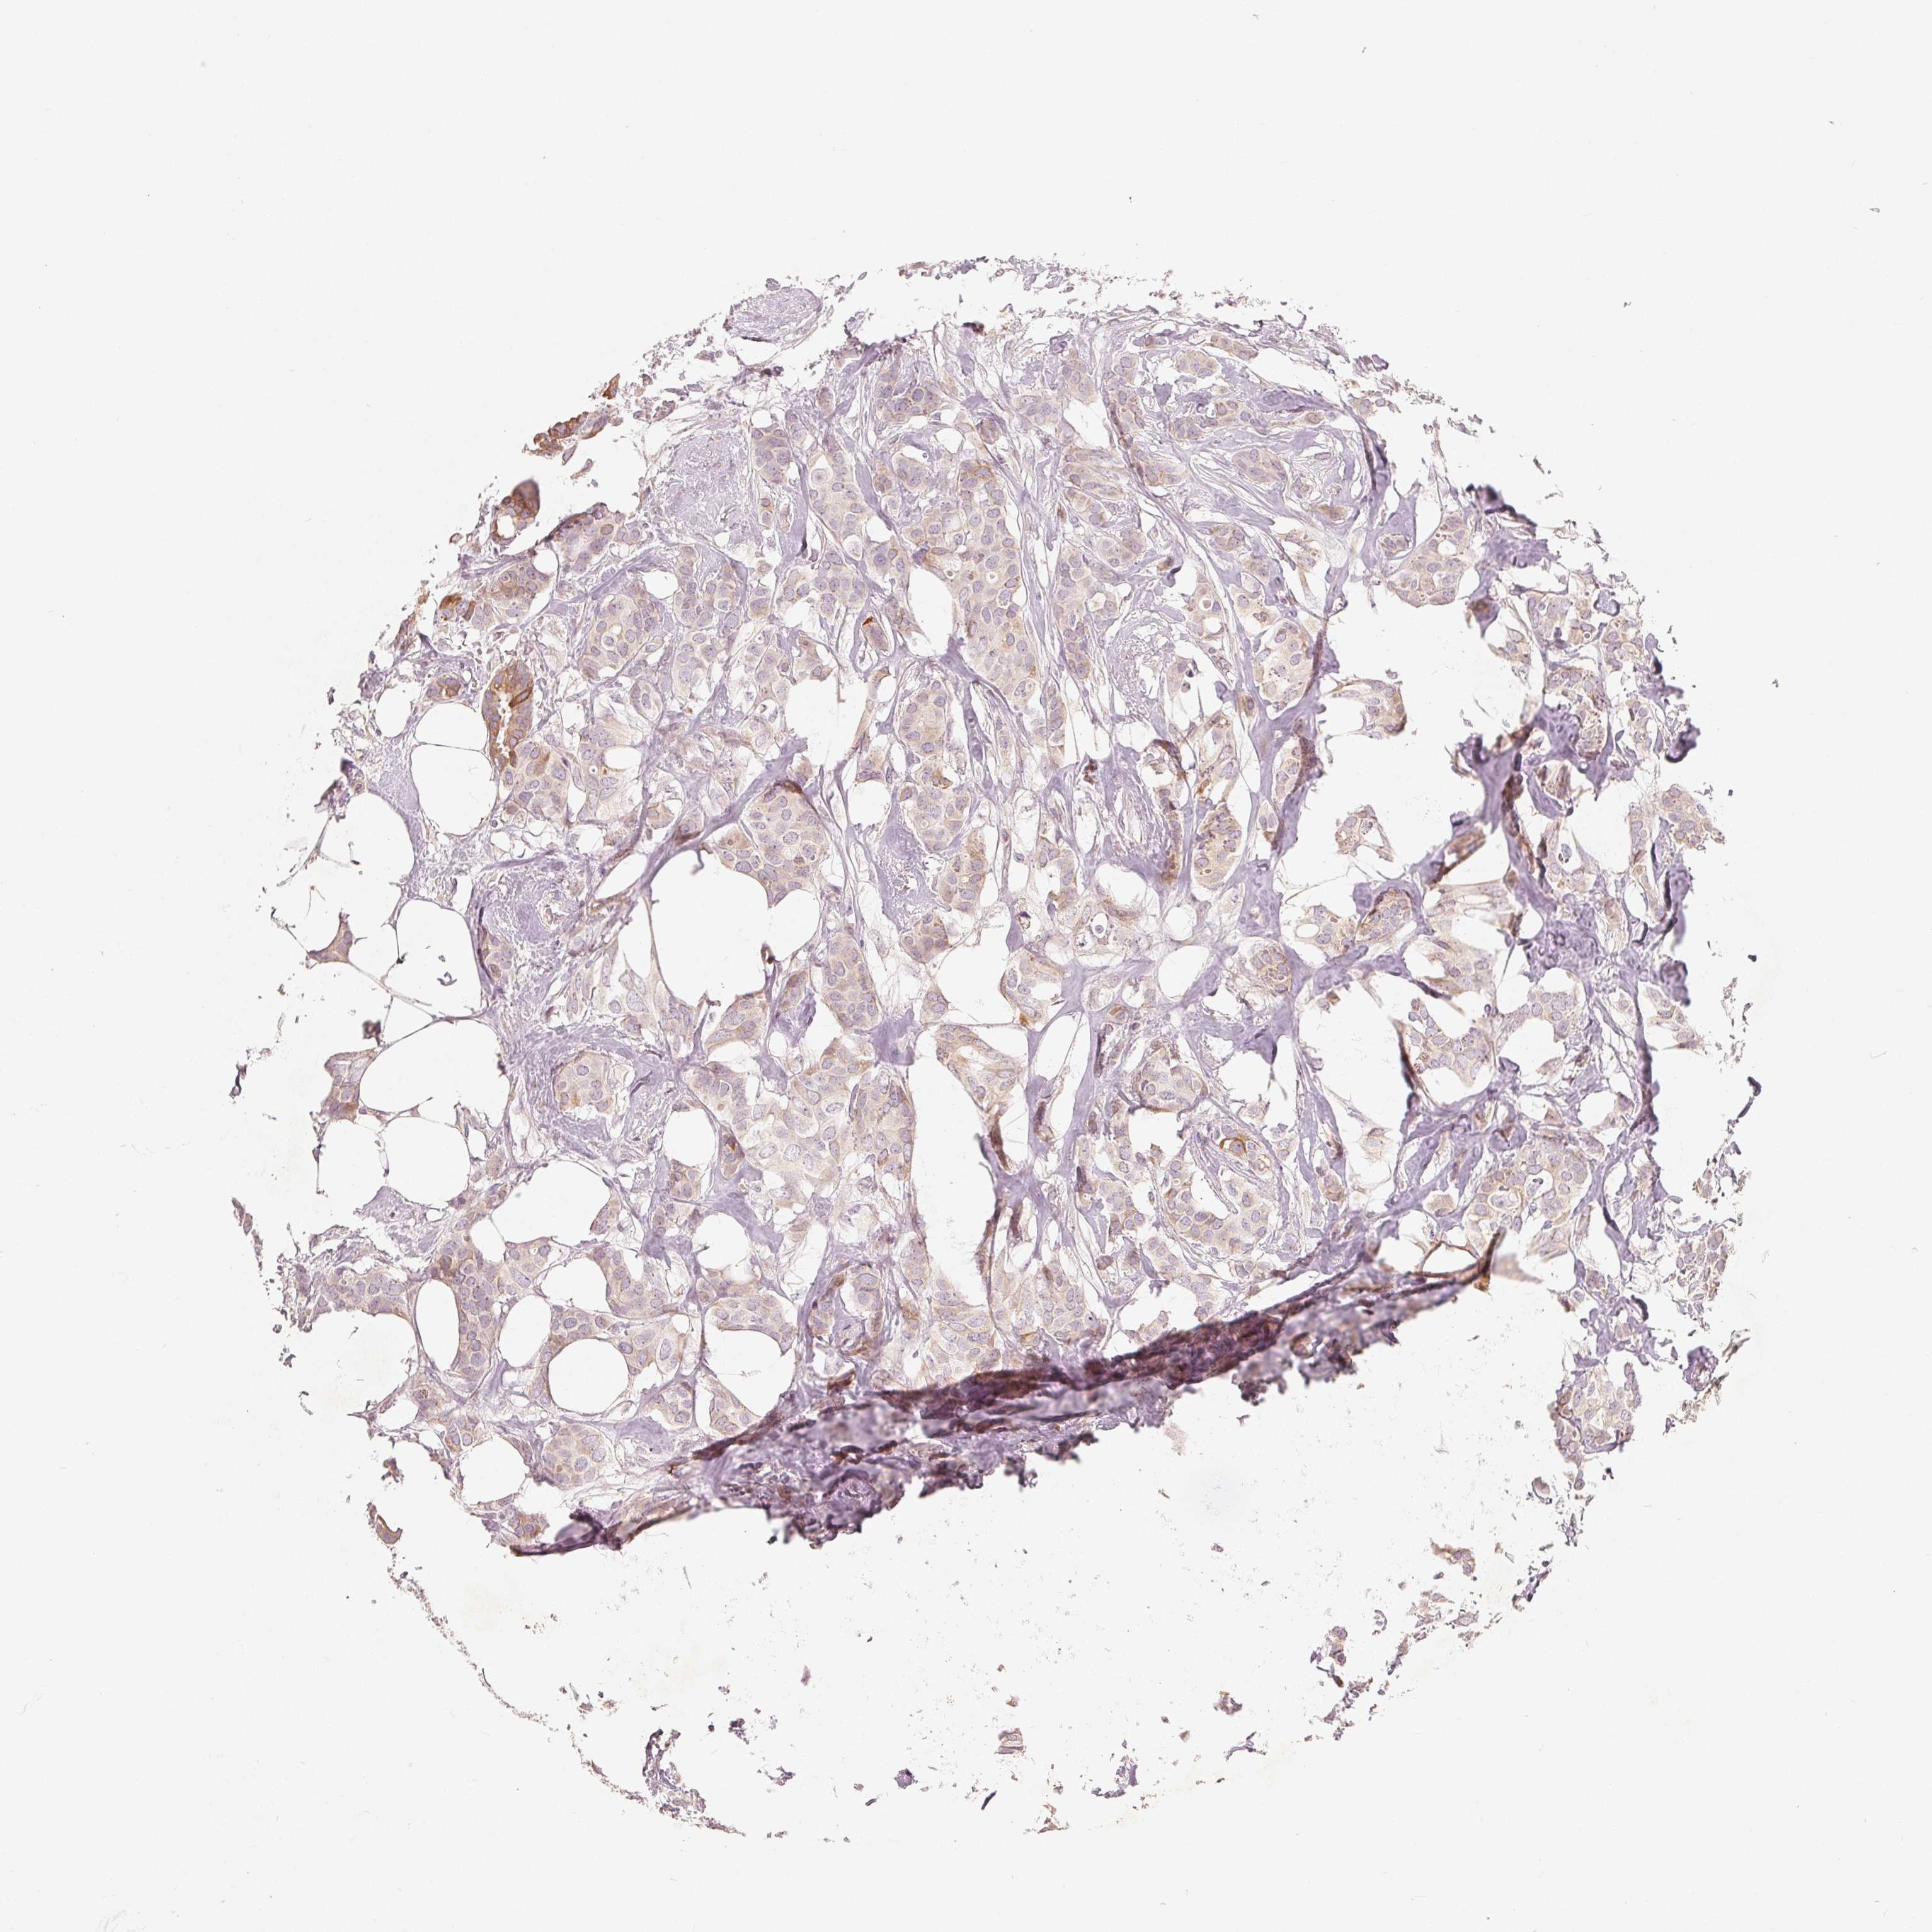

CANCER BREAST CANCER Show tissue menu

BRCA TCGA BRCA VALIDATION PROTEIN EXPRESSION